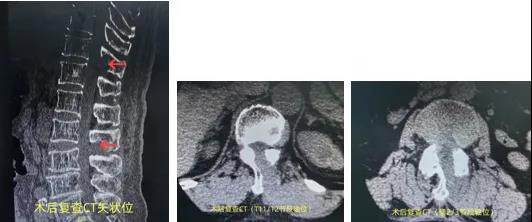

术后胸腰椎CT示:胸11/12、腰2/3节段术后、椎管减压充分。